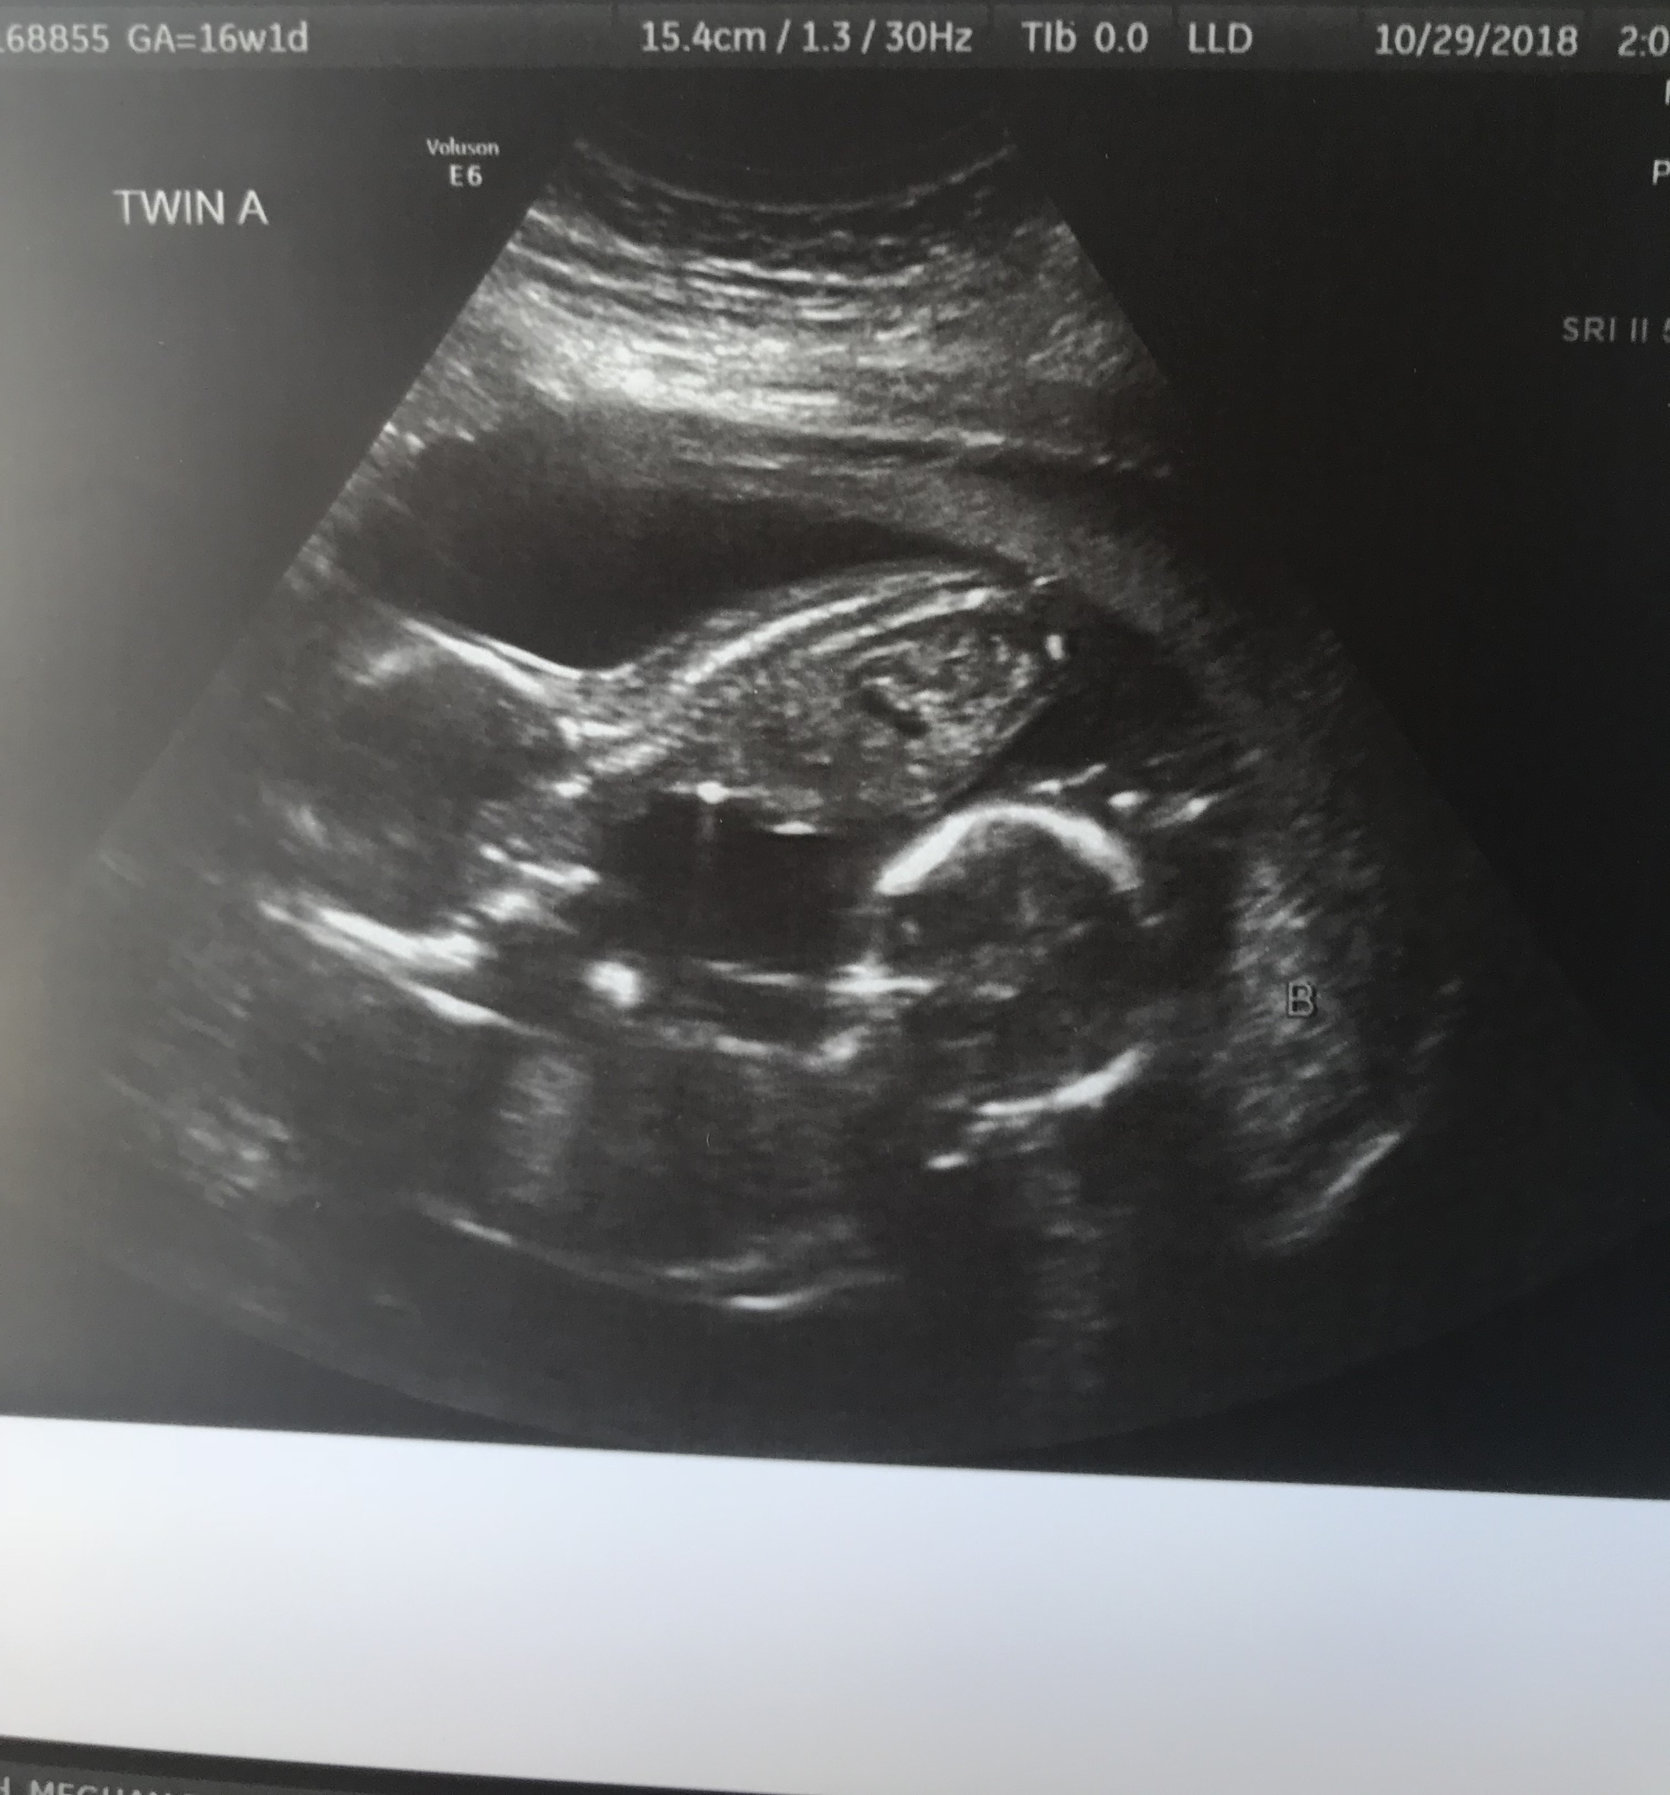

2. Pregnancy-related AW/vents/randoms for this week?

Just trying to figure out parental leave plans this week. Since we work in different countries (Sweden and Denmark) + the fact that we're having twins it's a bit tricky how the days will get split etc, but it does seem like we will get to stay home together for the fist bit which will be a relief (not sure how to manage breastfeeding two babies without having someone there to help me).

• @honey_suckle I'm definitely going out wider than I'd like, but currently the boys are laying side by side, one on my left and one on my right.